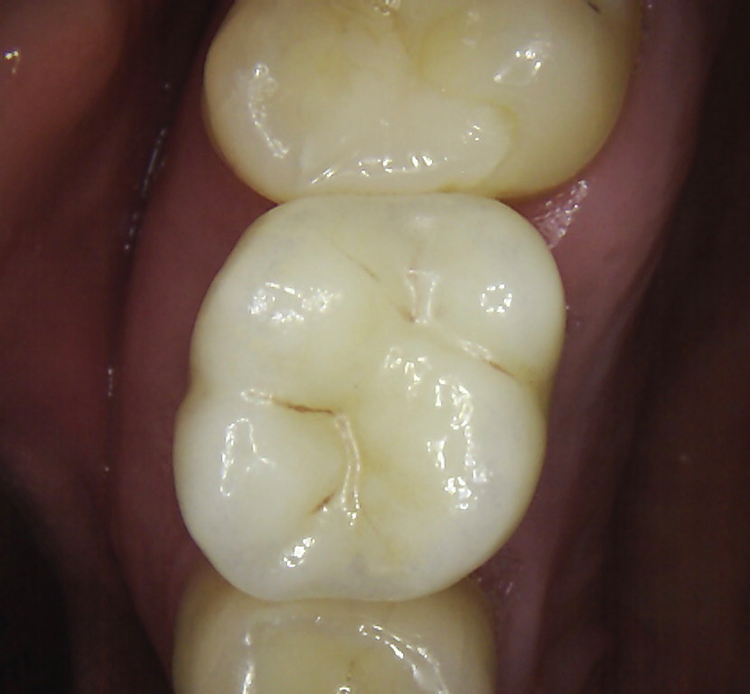

Abb. 2: Repräsentativer Fall von ABH Grad B Septus Typ II. a) Ansichten vor der Installation. Röntgenaufnahme der periapikalen Läsion an einem wurzelkanalbehandelten Molaren und klinische Ansicht der Typ-II-Socket nach der Extraktion. b) Die Ansichten nach der Installation zeigen das Implantat innerhalb des interradikulären Septums und das über dem Implantat platzierte A-PRF. c) Nachuntersuchungen nach 10 Tagen bzw. 2,1 Monaten. Die Röntgenaufnahme zeigt die Knochenbildung zwischen der Sinusmembran und dem apikalen Teil des Implantats. d) Jüngste Nachuntersuchung nach Einsetzen der Prothese.

Abb. 3: Repräsentativer Fall von Grad A Typ I. a) Präoperative Ansicht. Röntgenbild der periapikalen Läsion an einem wurzelkanalbehandelten Molaren. Die Höhe des Alveolarknochens zeigt Grad A an. b) Klinische und radiographische Ansicht der Implantatinsertion unter Verwendung einer Einheilscheibe mit großem Durchmesser (6×8 mm). A-PRF wurde um das Implantat und unter der Scheibe platziert. c) Nachuntersuchung nach 5,9 Monaten vor und nach der Zementierung und Aufbereitung. d) Jüngste Nachuntersuchung nach Einsetzen der Prothese

Die SDS-Zirkoniumdioxidimplantate wurden mit zementierten Pfosten weiter aufbereitet (Abb. 1d, 3 und 4c) und nach 4,74 + 0,95 Monaten Einheilzeit mit endgültigen Kronen versorgt. Die Balkonform ermöglichte ein natürliches Emergenzprofil, das die definitiven Kronen wie die Standardform ausrichtete sowie die Gesundheit des Weichgewebes und die Osseointegration förderte. Bei jeder Nachuntersuchung wurden Stabilität des Implantats, Zustand des umgebenden Gewebes und Vorhandensein von Zahnstein beurteilt.